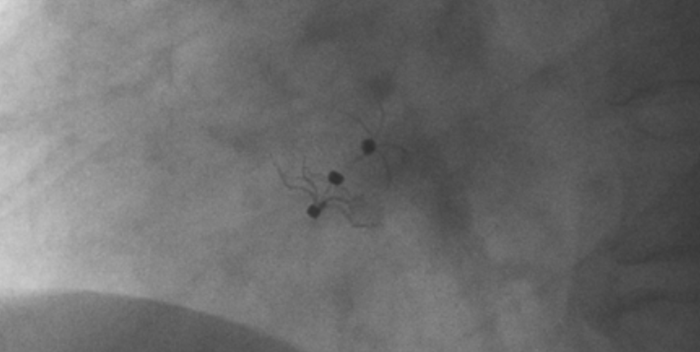

影像顯示試驗(yàn)器械適應(yīng)性貼合于房間隔兩側(cè)且穩(wěn)定

術(shù)中造影顯示患者為PFO且長隧道型,目前市場上已商業(yè)化的PFO封堵器難以滿足該患者解剖結(jié)構(gòu)封堵需求。迪創(chuàng)醫(yī)療自主研發(fā)的OmniSeal PFO封堵器自適應(yīng)性雙盤貼合設(shè)計能廣泛適應(yīng)不同PFO隧道長度的解剖結(jié)構(gòu)和形態(tài),其雙盤外包覆式阻流和隧道內(nèi)填充阻流相結(jié)合的雙重阻流設(shè)計,可為此患者實(shí)現(xiàn)有效封堵。與此同時,OmniSeal首創(chuàng)的完全可穿刺式設(shè)計,也為此患者最大程度地保留了房間隔區(qū)域穿刺通道,以實(shí)現(xiàn)全兼容未來可能的左心系統(tǒng)二次介入術(shù)。術(shù)終造影和心臟超聲顯示封堵完全、效果良好。作為OmniSeal的首例臨床應(yīng)用,本次手術(shù)的順利完成和優(yōu)異效果充分體現(xiàn)了產(chǎn)品的設(shè)計創(chuàng)新優(yōu)勢。